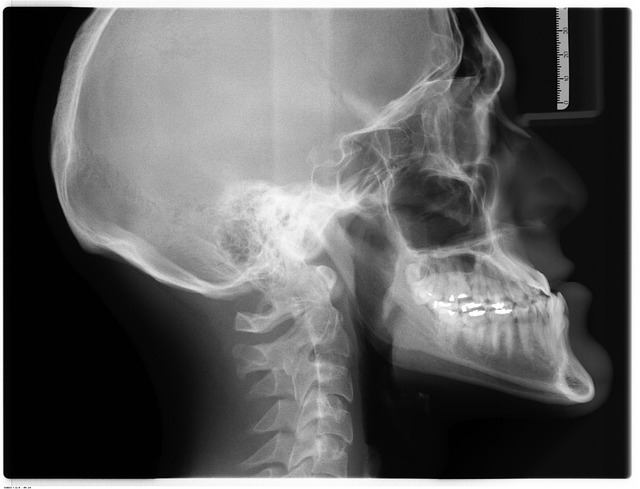

아데노이드 비대증은 아이들 중 매우 흔히 발생하는 건강 이슈 중 하나이며, 호흡곤란, 비염, 수면무호흡증 등 다양한 증상을 유발합니다. 비대증으로 인해 아이들이 숨쉬기가 힘들어지면, 입으로 숨을 쉬거나 바깥으로 내쉬기 때문에 공기 중 남아 있던 과다한 이산화탄소를 배출하기 힘들어집니다. 이러한 과정에서 긴 시간 동안 이산화탄소가 쌓이면서 아이의 얼굴이 변형됩니다. 이때, 과도한 조직이 얼굴 각 부분에 압력을 가하기 때문에, 그 결과 얼굴이 어긋나게 되고 "아데노이드형 얼굴"로 불리게 됩니다. 어떤 형태인지에 따라 발표 간격, 코 활약, 입술, 얼굴 각도 등이 변하거나, 짧은 턱, 얕은 고개 등이 나타날 수 있습니다.